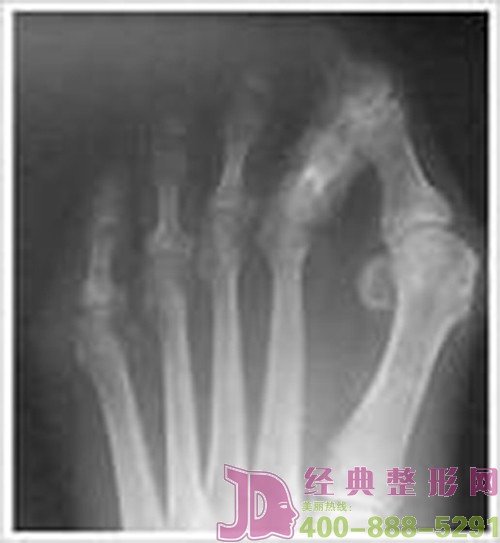

大腳骨是最常見的腳部畸形,多發(fā)生于女性。尤其喜歡穿高跟鞋,尖頭鞋的時(shí)髦女性非常多見。醫(yī)學(xué)上稱作拇外翻,俗稱大腳骨,與遺傳、穿鞋不適有很大關(guān)系。其表現(xiàn)為腳形難看,穿鞋變形,還伴有拇囊炎,疼痛。常常并發(fā)腳墊、雞眼、爪形趾等其他腳趾畸形。

2.足拇趾外翻、旋轉(zhuǎn)畸形。第二趾朝背面擠出,形成錘狀趾。前足變寬。

4.第一跖趾關(guān)節(jié)突出部皮膚增厚,甚至紅腫產(chǎn)生足拇囊炎。